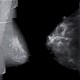

Das Röntgenbild zeigte eine Luxation der Metacarpale IV und V, sowie ein schalenförmiges knöchernes Fragment in Höhe der Basis von MC V auf der Seitaufnahme.

Die Diagnose einer Luxation oder Luxationsfraktur mit kleinen Fragmenten im Bereich der Basis der Mittelhandknochen ist nicht ganz einfach und kann röntgenologisch leicht übersehen werden. Die Luxation kann nur auf einer exakt seitlich eingestellter Röntgenaufnahme sicher erkannt werden.

Foto rechts: Hand in drei Ebenen: Carpo-metacarpale Luxation MC IV und MC V und kleines schalenförmige Fragment auf der seitl. Aufn. - Fotos: mta-r.de